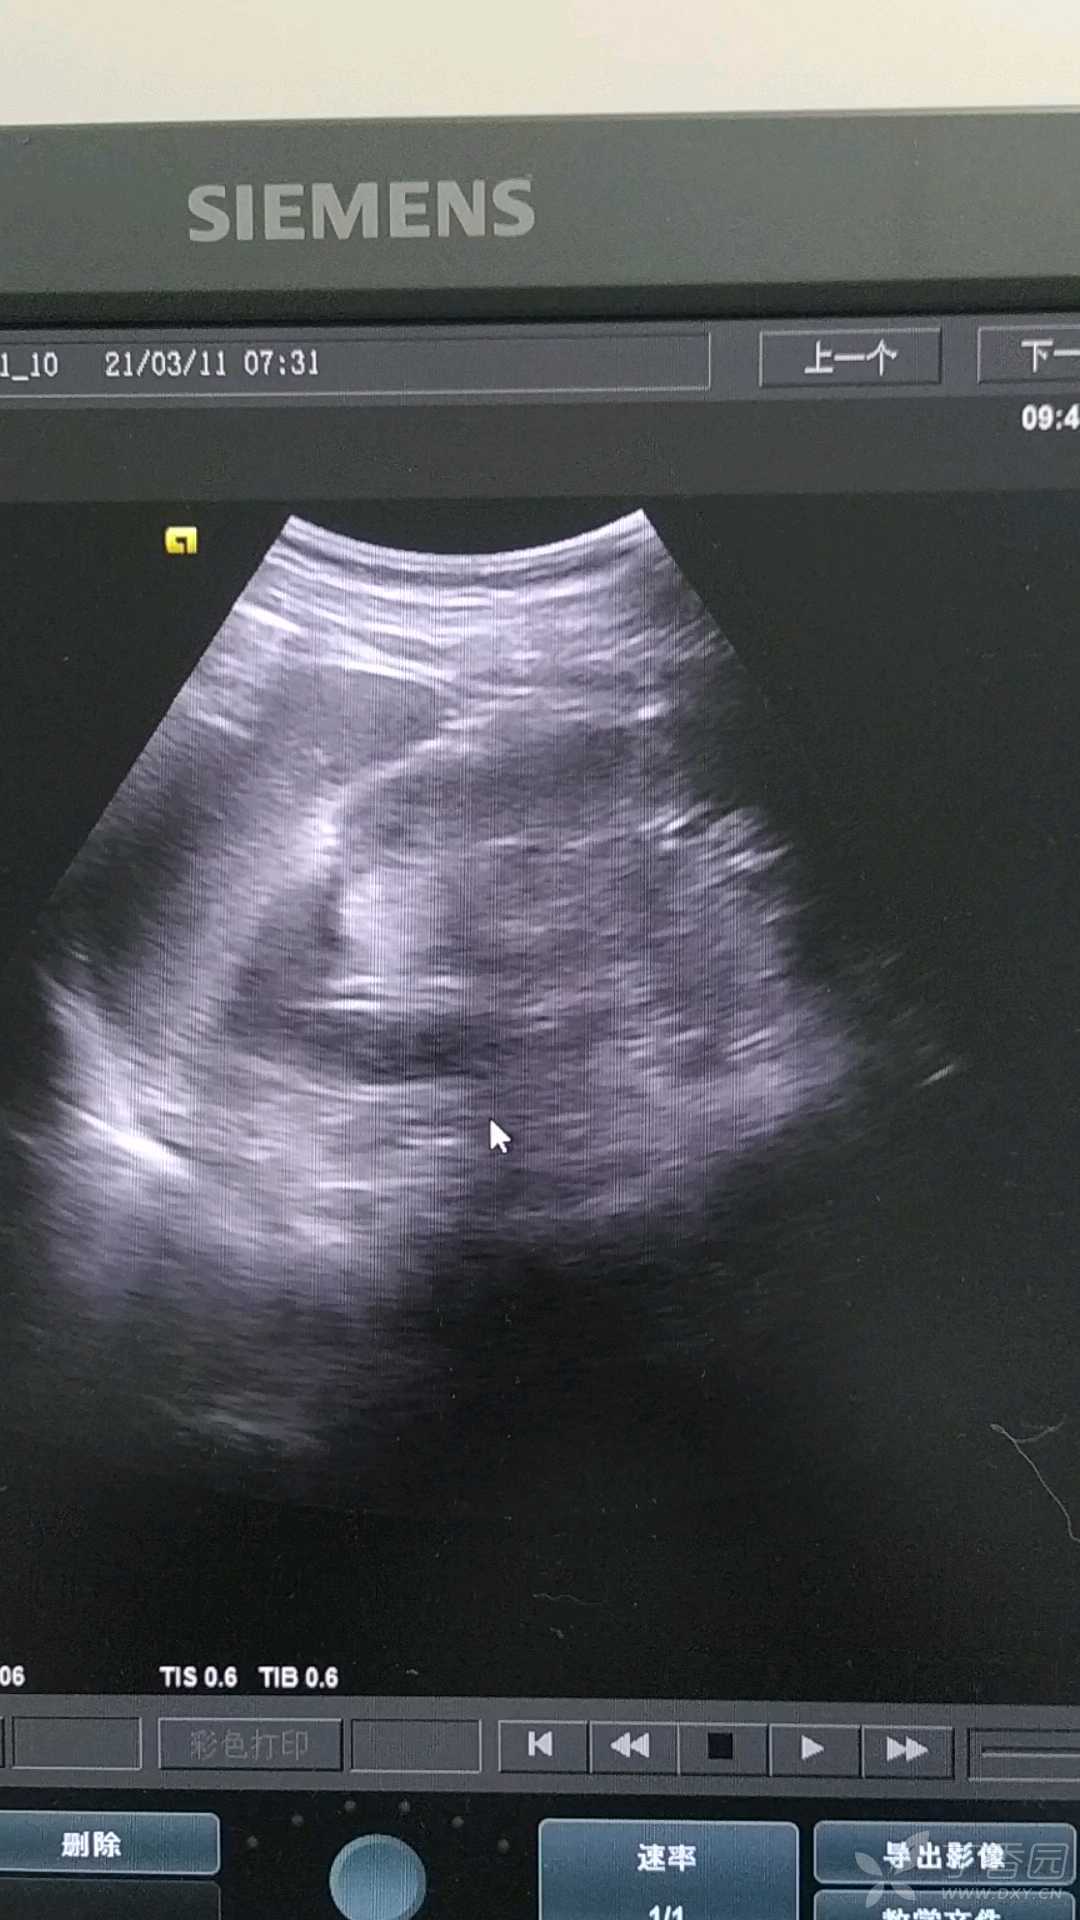

病例左肾窦内占位彩超与CT对比

男,58岁,体检发现左肾窦内可见高回声光团,患者自诉无血尿与不适,患者术后病理为肾癌